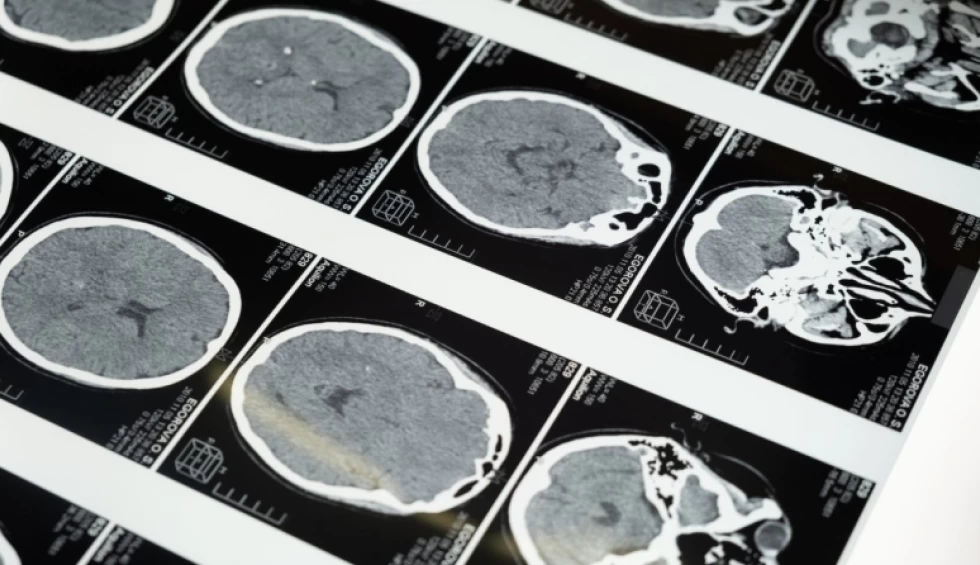

Μια νέα συναρπαστική μελέτη έριξε φως στο πόσο αξιοθαύμαστος είναι ο ανθρώπινος εγκέφαλος. Η έρευνα αφηγείται την ιστορία ενός άνδρα, γνωστού απλώς ως ασθενής Μ, ο οποίος πυροβολήθηκε στο κεφάλι κατά τη διάρκεια του ισπανικού εμφυλίου πολέμου της δεκαετίας του 1930.

Έγινε αντικείμενο έντονης γοητείας για τον Ισπανό νευροεπιστήμονα Justo Gonzalo, ο οποίος τον μελέτησε επί 50 χρόνια.Η ανάλυση του Gonzalo οδήγησε τελικά σε μια σημαντική αλλαγή στον τρόπο με τον οποίο κατανοούμε τον εγκέφαλο, κυρίως χάρη στο συμπέρασμά του ότι ο εγκέφαλος δεν είναι απλώς μια συλλογή διακριτών τμημάτων αλλά ένα δυναμικό σύνολο.

Ο ασθενής Μ βοήθησε τον νευρολόγο να δει ότι οι επιπτώσεις της εγκεφαλικής βλάβης εξαρτώνται από το μέγεθος και τη θέση του τραύματος και ότι οι τραυματισμοί δεν καταστρέφουν συγκεκριμένες λειτουργίες, αλλά επηρεάζουν την ισορροπία μιας σειράς λειτουργιών.